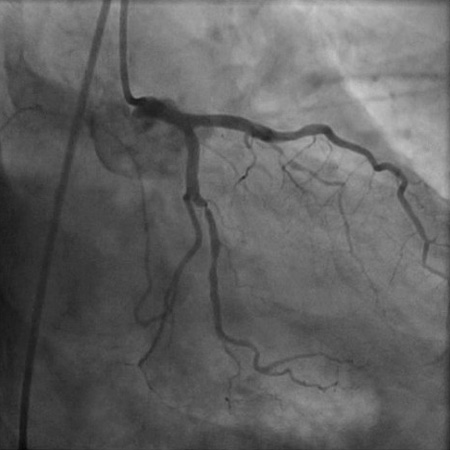

[Figure caption and citation for the preceding image starts]: Angiogram (right anterior oblique cranial projection) in a 55-year-old man with a 1-month history of angina on exertion. The image shows a 90% proximal stenosis of obtuse marginal 1 (explaining the patient's lateral ischaemia), 90% proximal stenosis of the first diagonal, and 99% subtotal occlusion of the second diagonal (explaining the patient's anterior and anterolateral ischaemia)From the collection of Dr S.D. Fihn; used with permission [Citation ends].